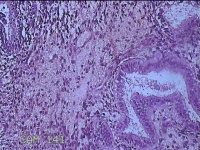

子宫腔赘生物

性别

女

年龄

33岁

临床诊断

子宫内膜息肉?子宫异常出血

一般病史

阴道流血12天。

标本名称

大体所见

灰白粉红色不规则肿物1.5x1.3x0.2cm一堆,表面糜烂。

图3